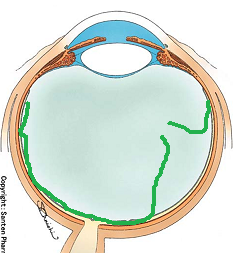

マリオット盲点以外の部位が欠ける場合は病気となるのですが、視野が欠ける代表的な疾患として、緑内障があります(日本人の失明の原因の第一位)。

マリオット盲点を認識しづらいのと同様に、実は、緑内障で視野が欠けた場合も初期の段階では気が付きにくいのです。(初めて病院に来る時には、末期だったんてことがよくあります。)